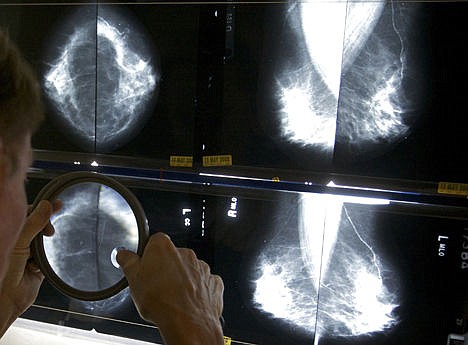

Breast cancer

The American Cancer Society has long recommended annual mammograms starting at age 40. The U.S. Preventive Services Task Force, which advises the government, said to get mammograms every other year from age 50 to 74, and says starting at age 40 brings little benefit but should be a personal choice if women are told the pros and cons.

The ACP sided with the task force's approach, saying even experts who prefer mammograms at 40 agree that women should be fully informed of the pros and cons to help them decide for themselves.

Routine screening isn't for 30-somethings, and more expensive MRI scans aren't for screening average-risk women, yet the ACP said doctors sometimes order both.